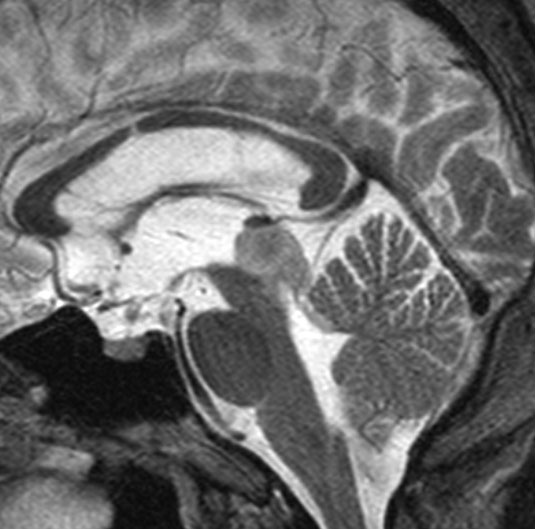

15歳時に水頭症で発症して増大しなかった例

この例が画像としては典型的な中脳視蓋グリオーマと言えます。手術摘出できないタイプです。

15歳の時に頭痛と嘔吐,視力と視野障害がでました。閉塞性水頭症だったので第3脳室開窓術を受けました。この時の診断は松果体腫瘍でした。でも翌年,開窓部が詰まってしまって,V-Pシャント(脳室腹腔短絡術)を受けました。でもシャントが詰まってしまって,頭痛と嘔吐と意識障害(昏睡、除脳硬直)を生じる急性シャント不全になり,シャント手術のやり直しをしました。21歳の時にもシャント不全で意識障害になり,シャント手術のやり直しをしました。その3ヶ月後にもまたシャント不全でシャント再建術を受けて,それから私の外来に来ました。

左はT1強調画像,右はFLAIR画像です。中脳視蓋が腫れて腫瘍がにじむように広がっているのがわかります。この腫瘍本体は15歳の時から21歳の時まで大きくなっていないので,中脳視蓋グリオーマ tectal gliomaの診断です。

T1強調ガドリニウム増強画像です。15歳の時は腫瘍の半分以上が強くガドリニウム増強されていましたが,この21歳の時の画像では,中心部やや右寄りに増強像が認められるだけです。この性質は,腫瘍が毛様細胞性星細胞腫であることを示しています。

左はT2強調画像,右はFLAIR画像です。中脳視蓋 tectum の中でも上丘が腫瘍化していることが解りますし,松果体は正常の大きさで腫瘍の上に乗っていますから,松果体腫瘍ではないことが解ります。上髄帆にも浸潤しています。

この患者さんは脳室の壁が硬くなってしまう slit ventricle syndromeのために,シャント不全でも脳室拡大しないで脳圧亢進が生じて,重篤な意識障害になっていました。治療は,確実に閉塞性水頭症を解除するために,前頭開頭手術で第3脳室の終板というところと灰白隆起の後ろ側を破る,脳室開窓術をしました。 その後にシャントを結紮して水頭症の悪化がないことを確かめてから,シャントを抜去しました。この手術の後,12年経ちますが医療関係の社会人として立派に生活しています。軽度の視野狭窄以外の後遺症(神経脱落症状)はありません。